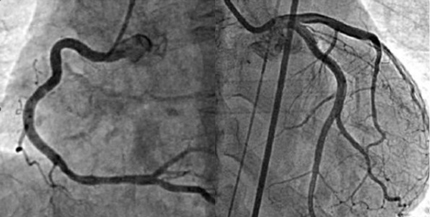

当科では、虚血性心疾患(狭心症・心筋梗塞)、心不全、不整脈、高血圧症などの循環器疾患全般について診療しています。心臓カテーテル検査、心臓超音波検査、各種心電図検査、心筋シンチグラフィー検査、MRI検査、PET検査などにより的確に診断し、適応があればさまざまな低侵襲カテーテル治療やリードレスを中心としたペースメーカー植え込み実施など、患者様の病状にあわせた治療を行っています。また、心疾患の予防からリハビリテーションまでの総合的治療も行っています。

2024年4月、新たに清岡崇彦(国際医療福祉大学教授)を循環器科部長に迎えました。清岡医師は、昨今注目を集め始めた原因不明の持続性胸痛(微小血管狭心症、冠微小循環障害CMD)の診断・治療において、まだほとんどこの疾患が知られていなかった15年以上前から、全国でいち早く診療や研究に取り組んできたスペシャリストです。

これまで当院で行ってきた急性期医療に加え、原因不明の持続性胸痛(冠微小循環障害 CMD)の診断・治療および心臓リハビリテーション(和温療法など)を強化し、これまで以上に的確な診断や治療をご提供できるようになりました。